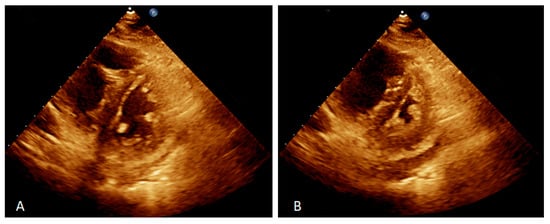

| Left ventricular ejection fraction | 59.7% |

| Systolic pulmonary artery pressure | 96 mmHg |

| Right ventricle size | 31 mm |

| RV index of myocardial performance | 0.64 |

| RV fractional area change | 21% |